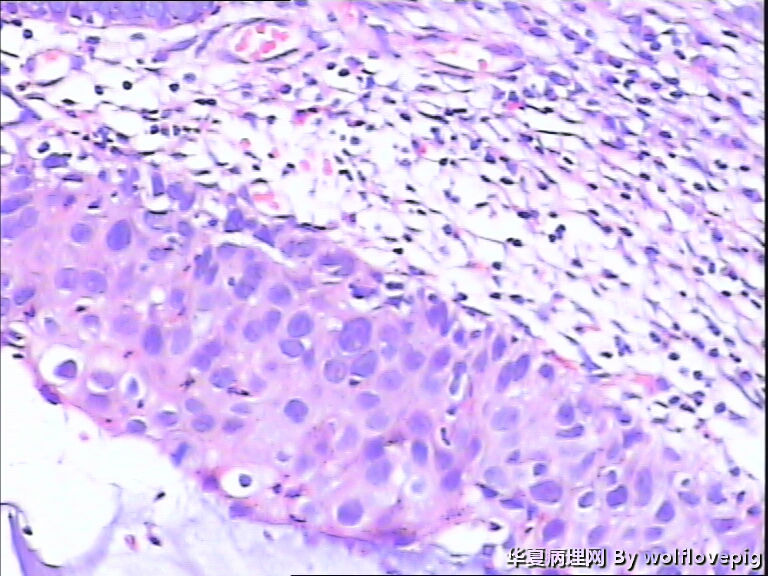

求助,宫颈!

37y

CIN3累腺

CINIII累及腺体

同意CINIII累及腺体

CIN-II 累及腺体。我看不够原位癌。学习了!

CIN2-3,累腺